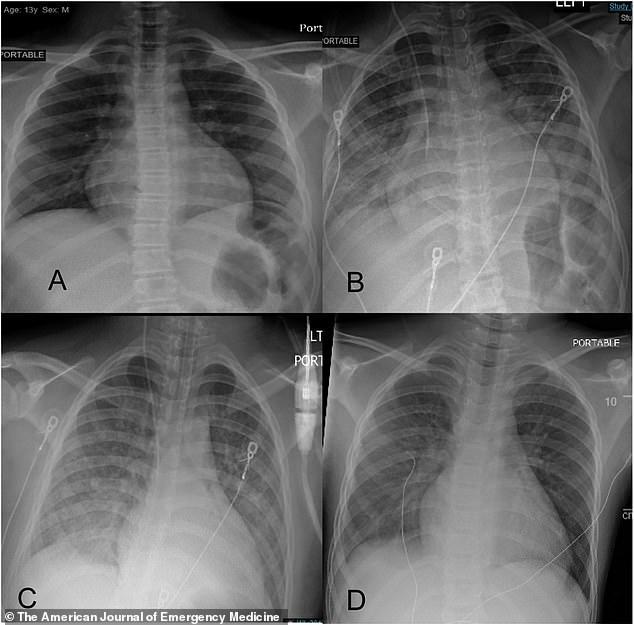

4月底至5月初 , 西奈山急诊室送来4名儿童患者 , 分别是15岁、12岁、5岁和10岁 , 他们的症状符合PMIS的标准 。 四个孩子都至少持续了一天的发烧 , 身上长满皮疹 , 他们还出现胃部不适 , 腹泻、腹痛或食欲不振 , 甚至心跳过速 。

四个孩子的新冠检测均为阴性 , 但抗体检测结果为阳性 。 其中一名儿童在两周前检测出冠状病毒阳性 。

入院后 , 孩子们的状况急速恶化 , 很快被送进了儿科重症监护室 , 他们出现PMIS和中毒性休克综合征 , 血液中有高水平的炎症标志物 。

现在 , 西奈山伊坎医学院的医生已经就此发布了第一份详细报告 。 研究中称 , 这四个孩子都有相同的“细胞因子风暴”标记物 , 即由异常免疫反应引发的过度炎症 , 常见于接受新冠病毒治疗的成年患者身上 。 这四名儿童患者中有三个是无症状感染者 , 入院后才出现重症 。